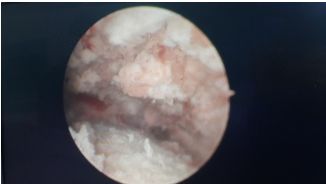

下面附诺舒治疗术后图片:

图1:宫腔内膜完全碳化